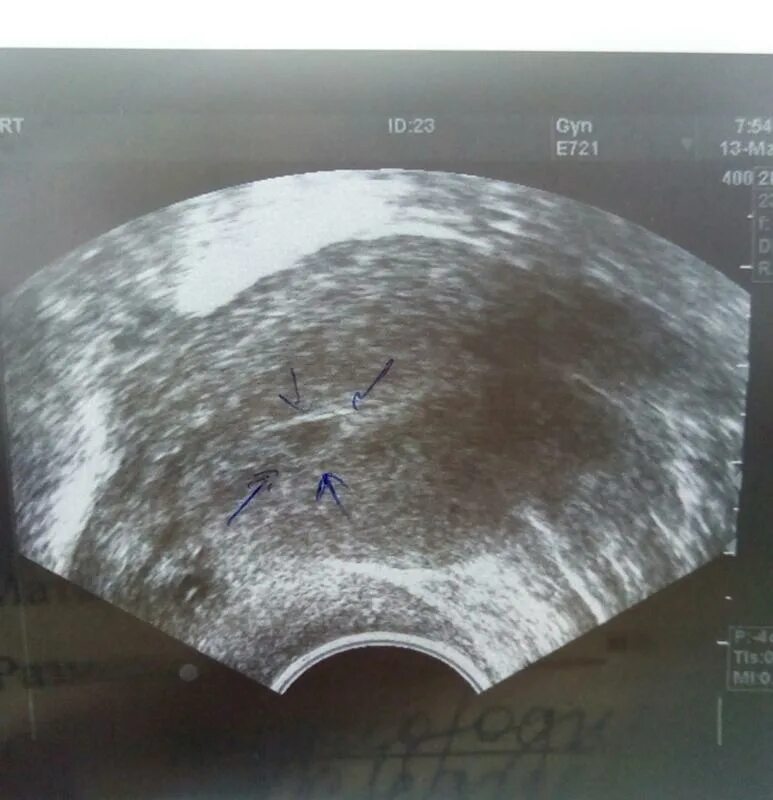

Белое пятно на узи